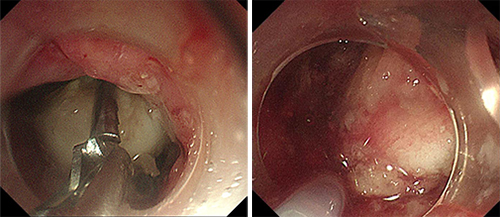

内镜手术在消化内科许洪伟主任指导下,由副主任医师李宾操作,刘华琳护士长配合操作。内镜下见异物巨大,嵌顿于食管上端致管腔扩张,异物钳无法夹持异物,更换圈套器后也无法套住异物。

尝试数分钟后,异物取出困难。李宾副主任医师当机立断,在许洪伟主任指导下更换内镜下用的胃石碎石器套取异物。胃石碎石器主要用于粉碎胃内结石,此次并不用于粉碎患者食管内的骨性异物,而是另辟蹊径,应用碎石器前端钢丝套住异物,再绷紧碎石器后端牢牢固定异物,调整牵拉方向,让患者做吞咽动作以松弛食管上段括约肌,成功拖出大小约4.0cm×2.5cm骨性异物。

整个内镜手术过程仅耗时13分钟。因异物过大且嵌顿于食管,碎石器钢丝取出后已弯曲变形,可以推断出普通内镜器械根本无法套取或牵拉住异物。如此大的异物在食管内存留3天,极易出现食管壁缺血、坏死,严重者可能出现食管穿孔。李宾副主任医师再次进入胃镜,发现原食管异物存留的位置,食管黏膜破损、溃疡明显,穿孔不能排除,在许洪伟主任指导下,给予放置胃管,行肠内营养,并协调消化内科病房石秀菊护士长安排患者住院进一步康复治疗。